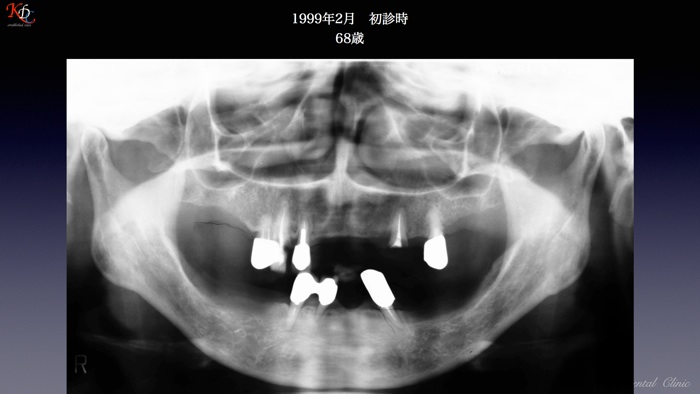

治 療例 1